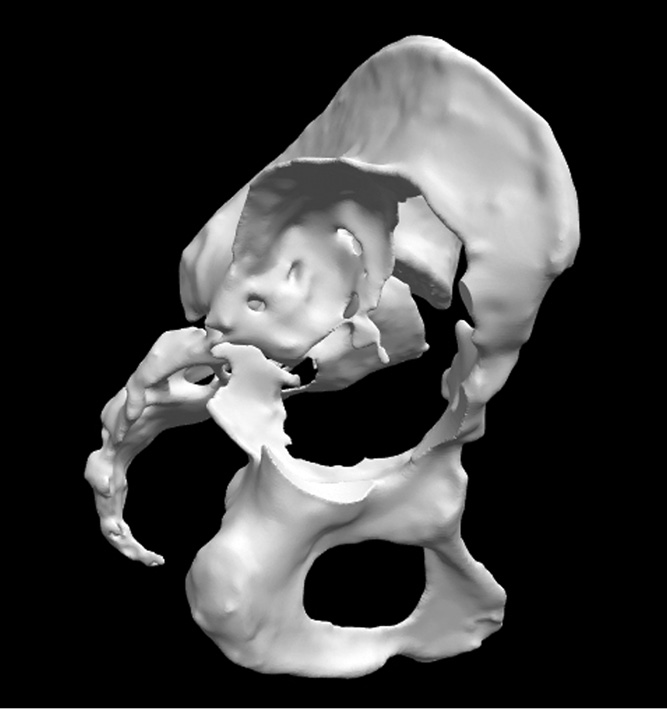

Учитывая выраженность костного дефекта вертлужной впадины, было принято решение об изготовлении индивидуального вертлужного компонента. Во время первой госпитализации пациентке было выполнено мультиспектральное компьютерно-томографическое (КТ) сканирование таза с минимальной толщиной среза, с интервалом 0,5 ± 0,1 мм для оценки потери костной массы. После обследования пациентка была выписана из стационара для повторной госпитализации при готовности имплантата.

Данные КТ были загружены в программу PMEPLanner. Инженером фирмы POLYGONMED, которые профессионально занимаются 3D-модели-рованием и печатью, произведен процесс сегментации, очищения от наводок и мягких тканей и создание цифровой 3D-модели пораженной стороны таза (рис. 10, 11).

Рис. 10. Компьютерно Т-изображение пораженной части таза после обработки и очищения от наводок, мягких тканей

Рис. 11. Вид модели таза с разных сторон. Визуализация дефектов вертлужной впадины с точностью до 1 мм